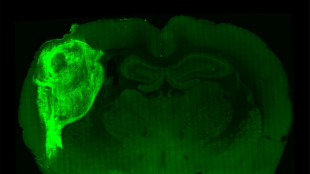

Implantan células del cerebro humano en ratas para estudiar desórdenes psiquiátricos

Un grupo de científicos implantó e integró con éxito células del cerebro humano en ratas recién nacidas, creando una nueva forma de estudiar enfermedades psiquiátricas como la esquizofrenia o el autismo.